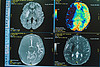

– Такой случай в нашей практике произошел впервые. Мы начали искать пути лечения, которые помогут спасти жизнь ребенку. Важно понимать, что лечение детей и взрослых очень сильно отличается. Совместными усилиями с коллегами мы выстроили правильный план лечения, для контроля ситуации ежедневно в динамике проводили магнитно-резонансную томографию, а также терапию согласно клиническим рекомендациям. В результате удалось вывести нашу маленькую пациентку из острого состояния, – добавила Наталья Муратова.